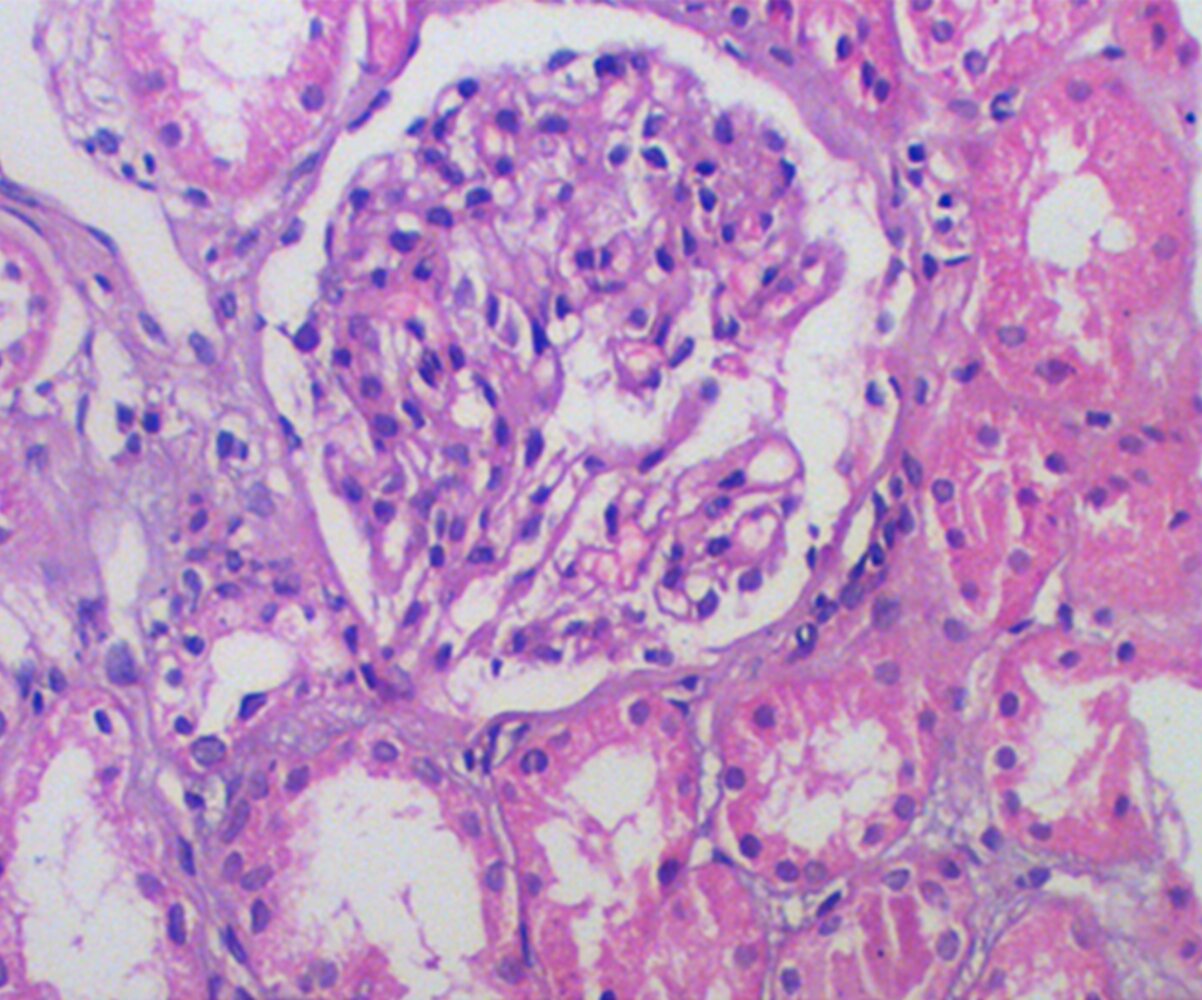

• Light microscopy: mesangial cell proliferation and sclerosis